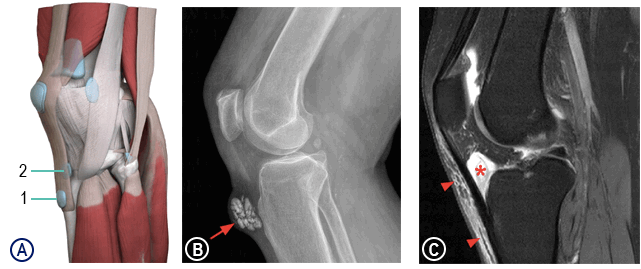

А – расположение поднадколенниковой поверхностной сумки (1) и поднадколенниковой глубокой сумки (2)

В – хронический кальцифицированный поверхностный инфрапателлярный бурсит

С – посттравматический глубокий инфрапателлярный бурсит: растяжение глубокой инфрапателлярной сумки с небольшим количеством синовита (звездочка), умеренный подкожный отек в передней части колена, чуть ниже коленной чашечки (стрелки)